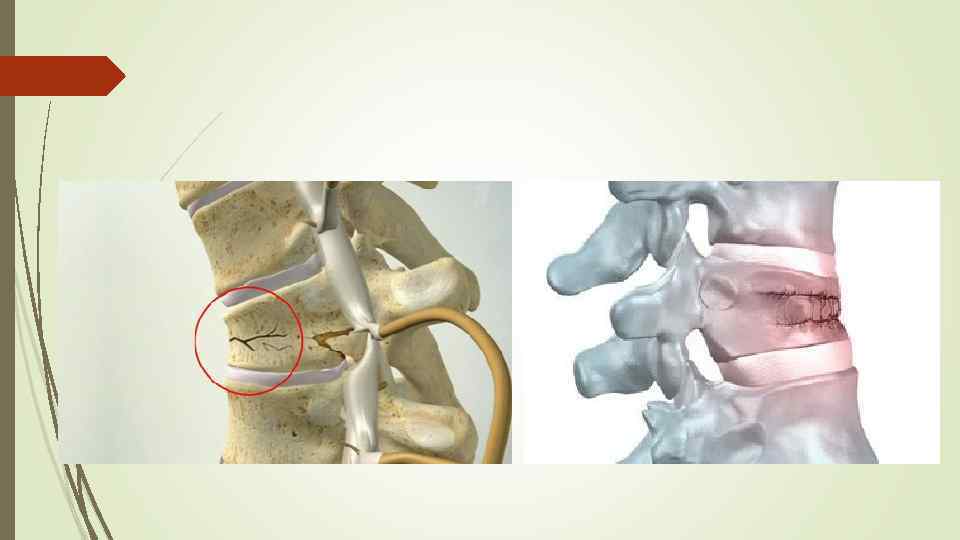

Вертебропластика и фибропластика относятся к современным методам лечения компрессионного перелома позвоночника. Такие методы позволяют более эффективно устранять повреждения костной ткани, что значительно снижает время лечения и реабилитации компрессионного перелома позвоночника.

Кифопластика – это такой метод лечения компрессионного перелома позвоночника, при котором сначала восстанавливается нормальная высота повреждённого позвонка, а затем вводится цементирующий раствор. Такой метод лечения восстанавливает позвонок в его нормальном положении.